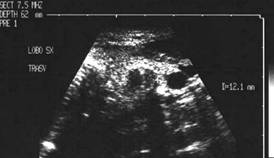

Sonda convexa de 5.0 MHz,

Sonda liniara de 10.0 MHz, proiectie trasversala si longitudinala a lobului

stang.

Pacienta de 28 ani. Voluminoasa tumefactie a lobului

stg., marcant hipoecogena, cu intarire posterioara, de 38x45x69mm.

La aspiratie, circa 60 cc de coloid foarte dens.